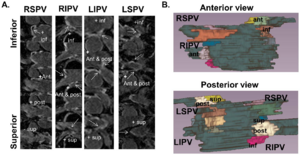

- 4.12 Cardiovascular Magnetic Resonance Imaging of Scar Development Following Pulmonary Vein Isolation: A Prospective Study

|